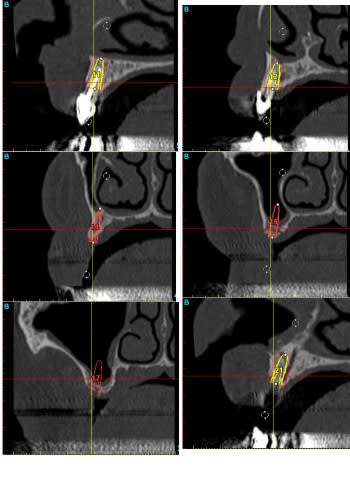

alors je vous adresse le scan et vous me dites si compte tenu de l'occlusion et sans greffe vous auriez fait moins?

Vk1 u5ulfa - Eugenol

Vk2 dvyxdc - Eugenol

P1010130 jpci1f - Eugenol

Et bien les voilà tes raisons, Scan abominable et pas d'os du tout.

Je savais bien qu'il devait y avoir un truc.

C'est déjà un bel exploit, Pxav, d'avoir pu lui poser des implants sans greffe, bravo.

> Et bien les voilà tes raisons, Scan abominable et pas d'os du tout.

bien sur 12 implants c'est énorme pour un complet amovo-inamovible.

mais quelle galère, en reallité je crois me souvenir (je n'ai pas la fiche) avoir utilisé 15 implants (3 "reprises")

mais en regardant le scan, suite à votre remarque, et parce que je prépare ma présentation du 17/12, je pense qu'il fallait ça.

vu le scan, j'aurais pas été capable sans greffes.